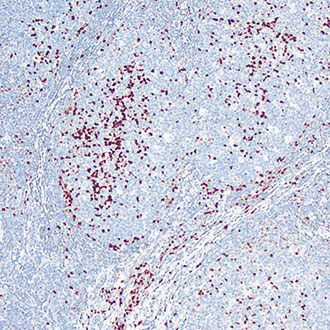

CD8

CD8 -